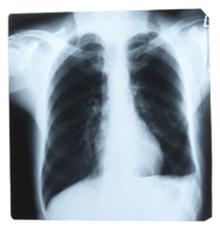

* sub aspect diagnostic descoperirea in timp util a cazurilor de tuberculoza intampina in practica diificultati notabile explicate prin polimorfismul derutant al manifestarilor bolii. Desi localizarea ei preponderenta este cea pulmonara (peste 75% din cazuri) numeroase alte organe si tesuturi pot atinse (pleura, ganglioni limfatici periferici, oase si articulatii, tractus urogenital s.a. ) . Dar, indiferent de localizare, tuberculoza imbraca o gama larga de forme clinice, unele tipice dar numeroase, altele atipice, atat prin tabloul initial, cat si prin tendinta evolutiva (de la forme asimptotice sau torpide, pana la forme acute sau supraacute) . In plus, factorul varsta imprima tabloul clinic al bolii diferente esentiale (ex.: tuberculoza copilului de varsta mica fata de ftizia adultului) .

Daca in organism este prezenta forma latenta a tuberculozei, nu exista simptome si aceasta nu poate fi raspandita altor persoane. Daca exista forma activa a tuberculozei, exista simptome si infectia poate fi raspandita. Tipul simptomelor sunt in concordanta cu tipul de tuberculoza fie pulmonara (cel mai comun), fie in alta parte a corpului (tuberculoza extrapulmonara). De asemenea pot exista alte afectiuni cu simptome asemanatoare cu cele ale tuberculozei cum ar fi pneumonia si cancerul pulmonar. |

Diagnosticul bacteriologic al tuberculozei pulmonare

Examinarea unui singur esantion de sputa nu este in regula suficienta pentru identificarea bacililor tuberculosi in sputele paucibacilare sau intermitent pozitive. Pentru acest motiv in practica ftiziologica a devenit uzuala recoltarea repetata a sputei in 3 zile consecutive. Pentru imaginile radiologice aparent inactive sau de activitate dubioasa (leziuni nodulare, leziuni minime, leziuni sechelare) este indicata examinarea unui numar mai mare de esantioane de sputa (6-10) prin cultura.